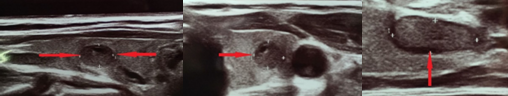

FiFigures 2,3,4 . Thyroid U/S . Encapsulated medullary microcarcinoma . (Courtesy Dr . V . Penopoulos) .